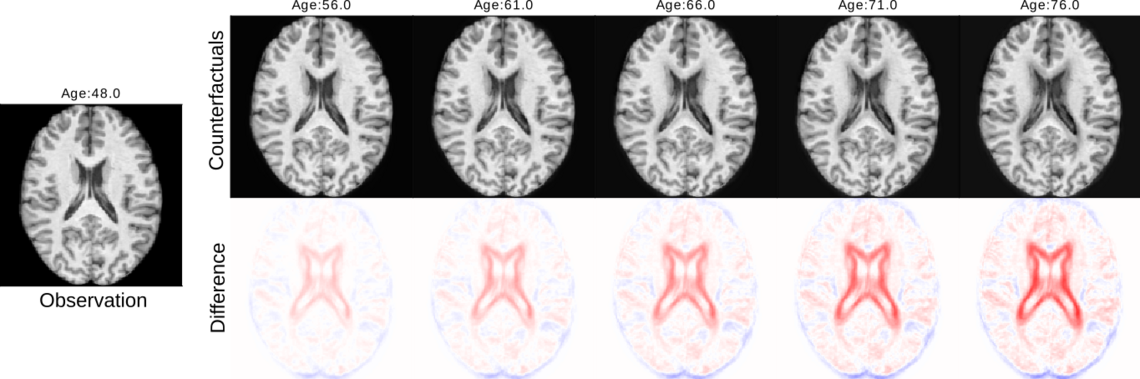

Integrating causal structures into generative models with masked causal flow (MACAW)

While deep learning techniques show promising results in neuroimaging tasks on theoretical grounds, they have not yet found widespread use in clinical settings. One of the reasons behind this is the inherent complexity and lack of transparency associated with these models. To tackle this issue, numerous explainable AI (XAI) techniques have been developed. However, many of these methods are primarily post-hoc, which might not fully capture the model's actual behavior. This project focuses on developing a novel deep learning architecture called Masked Causal Flow (MACAW), which combines the advancements of Causal AI and generative modelling.